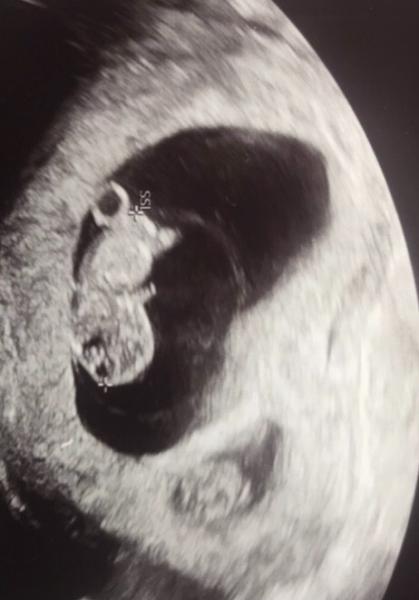

Ich hänge mal Fotos an von Kind 1 und Kind 2. Die Ärztin hat gesagt, noch wäre bei dem in der kleinen Fruchthöhle alles drin. Herzschlag war da, aber die winzige Fruchthöhle macht mir Sorgen…

Bild zu